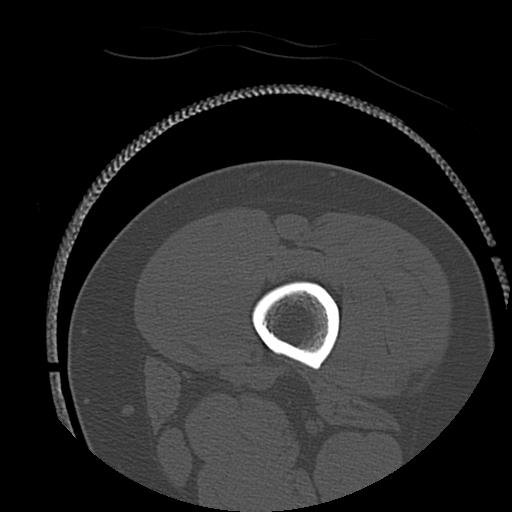

56476 8/28 4R 1/21 2R 左足関節 デジカメ写真 72歳女性 右足関節AS